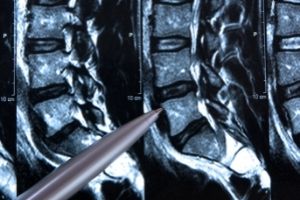

Neurochirurgen können anhand des Beschwerdebildes, des körperlichen Untersuchungsbefundes und in der Regel auch weiterführender Untersuchungen (z. B. der Kernspintomographie) genau feststellen, wo das Problem liegt. Auf Grundlage dieser Diagnose kann dann eine zielgerichtete Therapie eingeleitet werden. Dabei ist es in den meisten Fällen möglich, nicht-operativ zu behandeln.

Unter CT-geführten Injektionen versteht man Spritzen, die unter computertomographischer Kontrolle in die Nähe der Wirbelsäule – meist an die kleinen Wirbelgelenke (Facetten) – eingebracht werden. Vorteil dieses Verfahrens ist, dass mit Hilfe der Computertomographie die optimale Position der Nadeln sehr exakt zu bestimmen ist.